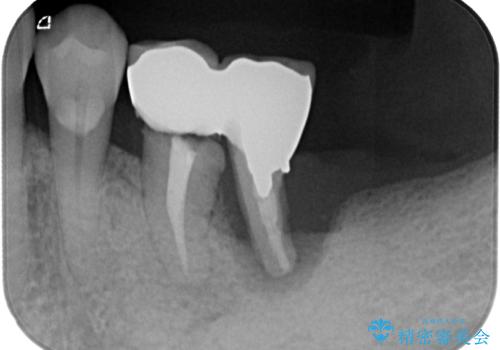

- 連結されている奥歯がグラグラしていて、インプラント治療を希望して来院された患者様です。

連結の手前の歯は歯根が破折して、クラウンが歯から外れており、奥の歯は動揺により歯根周辺の骨が吸収している状態でした。

骨吸収が甚大な後方は3ヶ月ほど待機して、手前は抜歯即時埋入により、短期間インプラント補綴治療を行うこととしました。